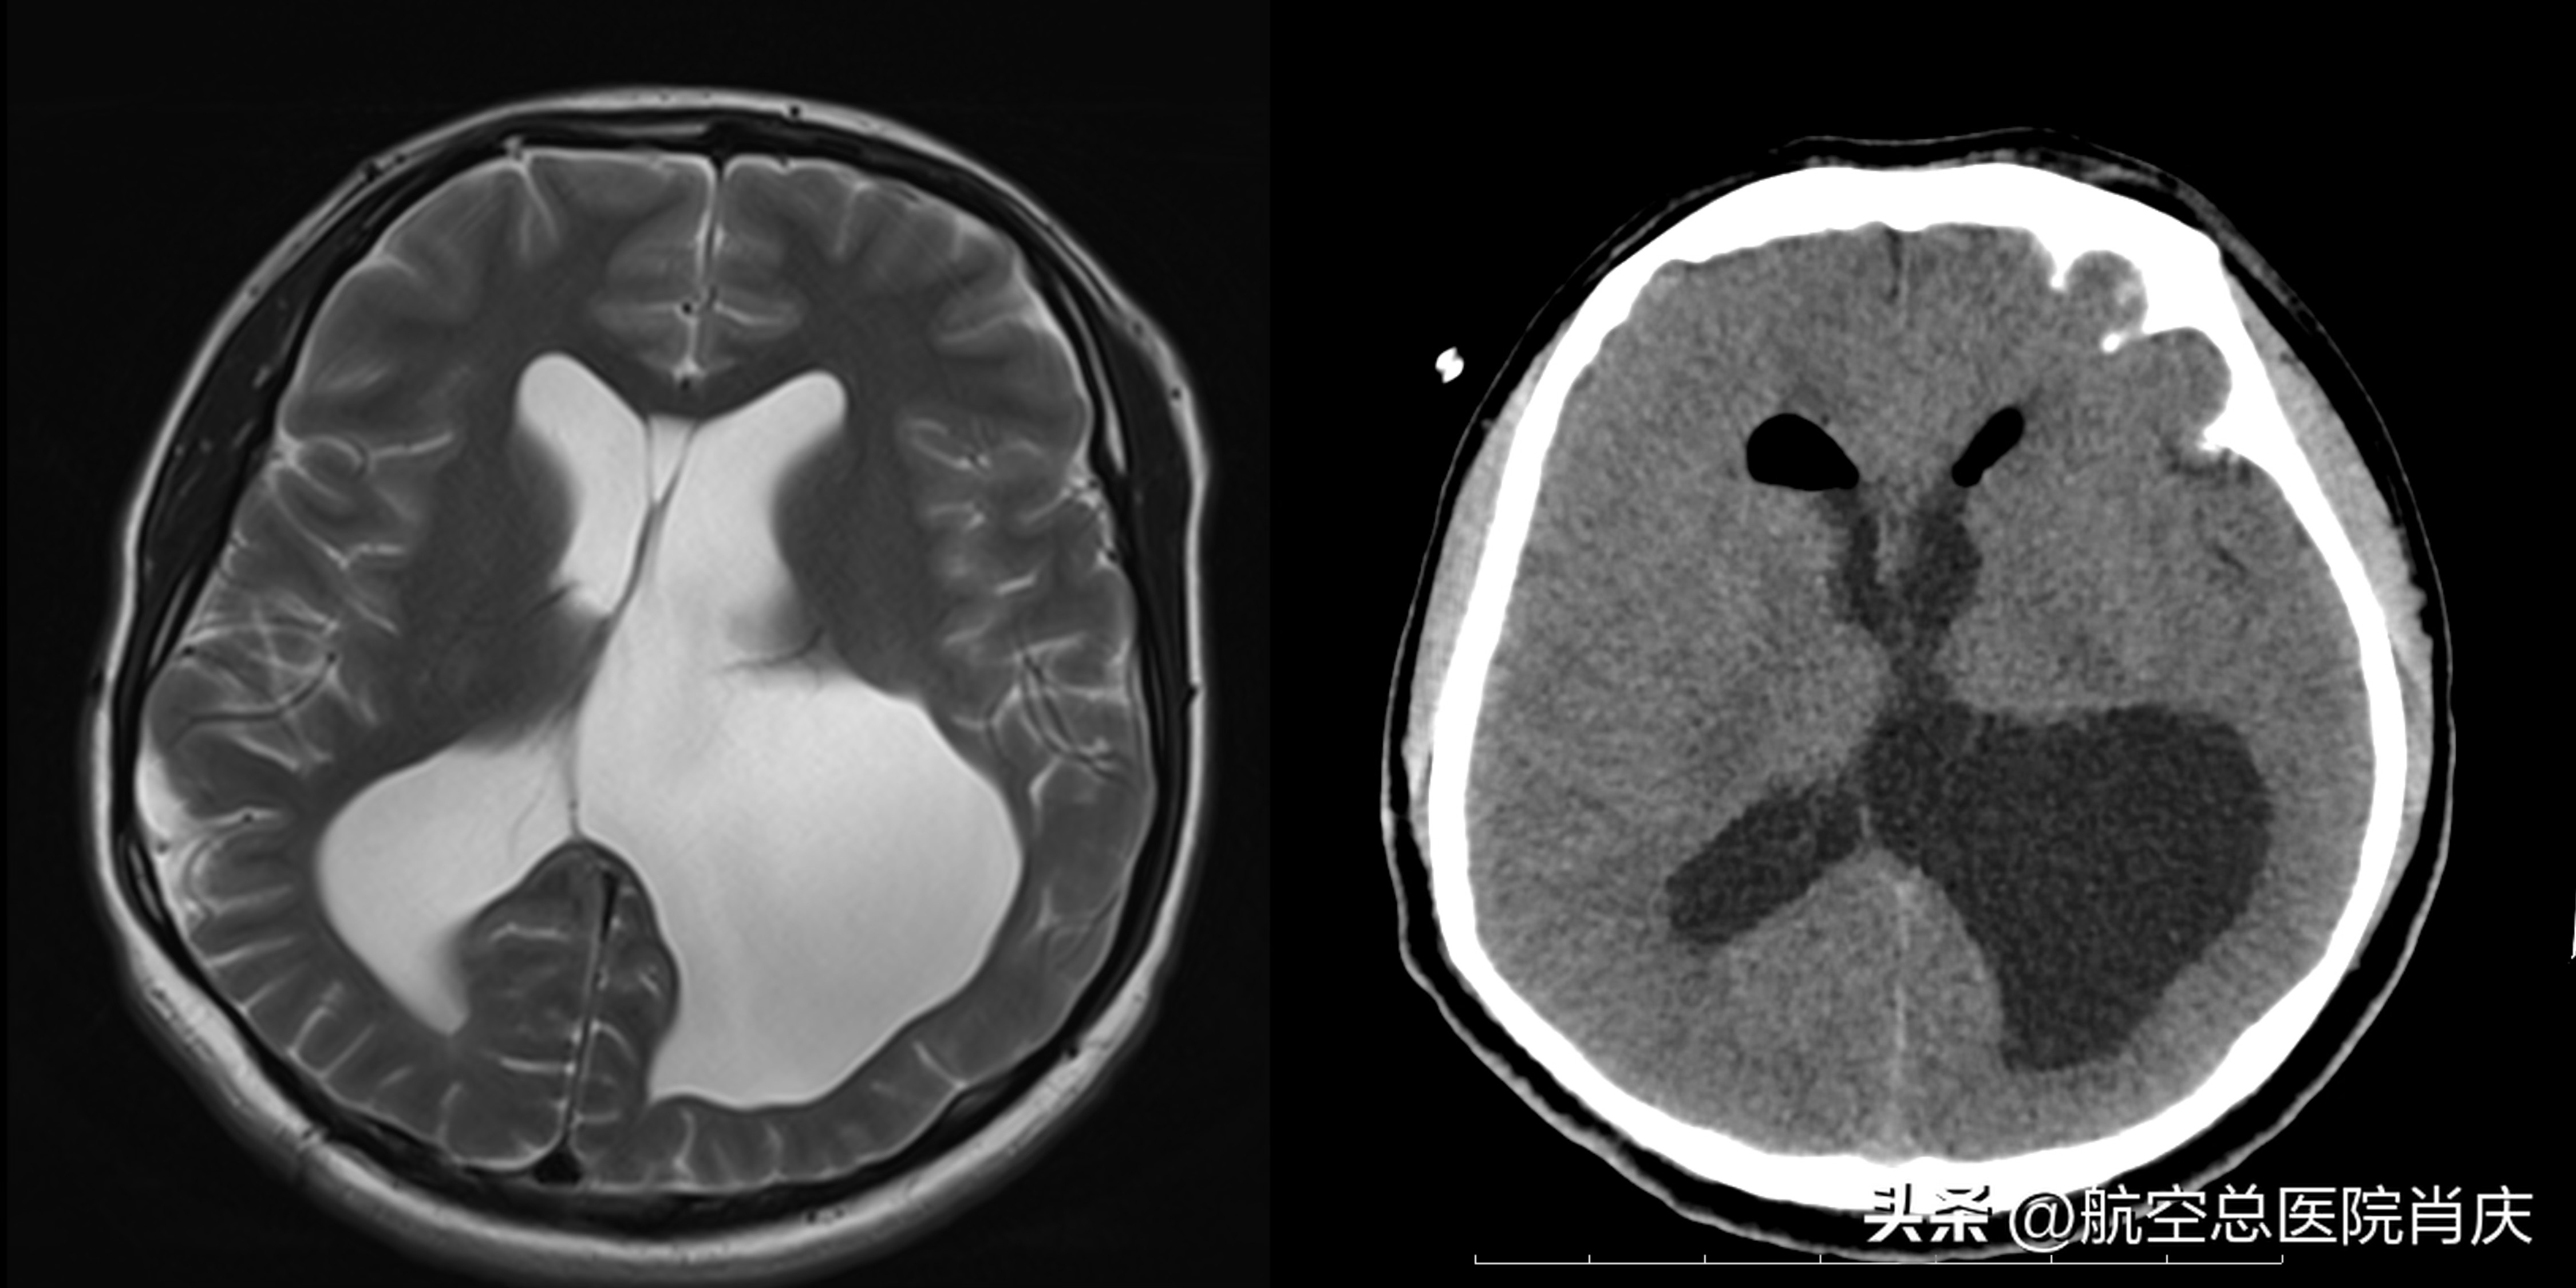

术前术后对比轴位

半年前,甘肃的患者王先生发现自己右侧胳膊和腿变得有些不一样,跟左侧比起来肌肉力量弱还肉眼可见的要细,活动起来也不灵活,使不上劲。几经辗转求医来到了我院神经内科就诊,进一步查头颅MRI示胼胝体体部及压部缺如,幕上脑室扩大,阻塞性脑积水或脑发育不全、右侧颞叶软化灶或发育不全。小腿神经电生理检查未见异常,小腿肌肉活检提示符合进行性肌营养不良。经腰椎穿刺后症状有所改善。